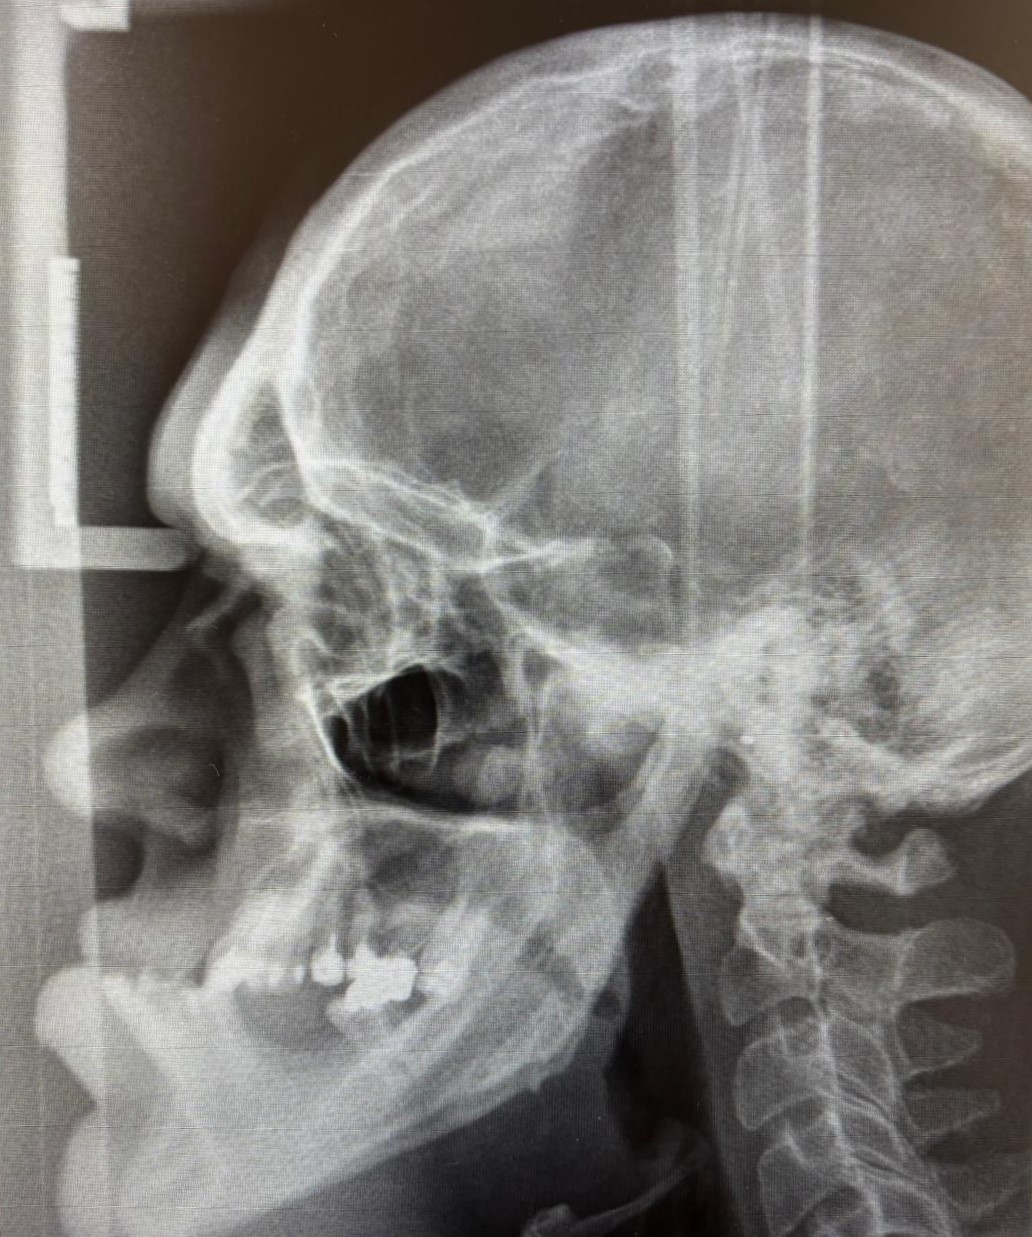

A acromegalia é uma doença rara causada, na maioria dos casos, por um adenoma hipofisário produtor de hormona de crescimento (GH). A sua prevalência é estimada em cerca de 40 a 70 casos por milhão de habitantes, mas acredita-se que esteja subdiagnosticada, uma vez que os sintomas se instalam de forma lenta e insidiosa.

Entre as suas principais manifestações clínicas destacam-se o aumento progressivo das mãos, pés e traços faciais, dores articulares, alterações metabólicas (como diabetes ou hipertensão) e complicações cardiovasculares. Estas alterações, quando não reconhecidas precocemente, podem ter um impacto significativo no aspeto e na qualidade de vida dos doentes.